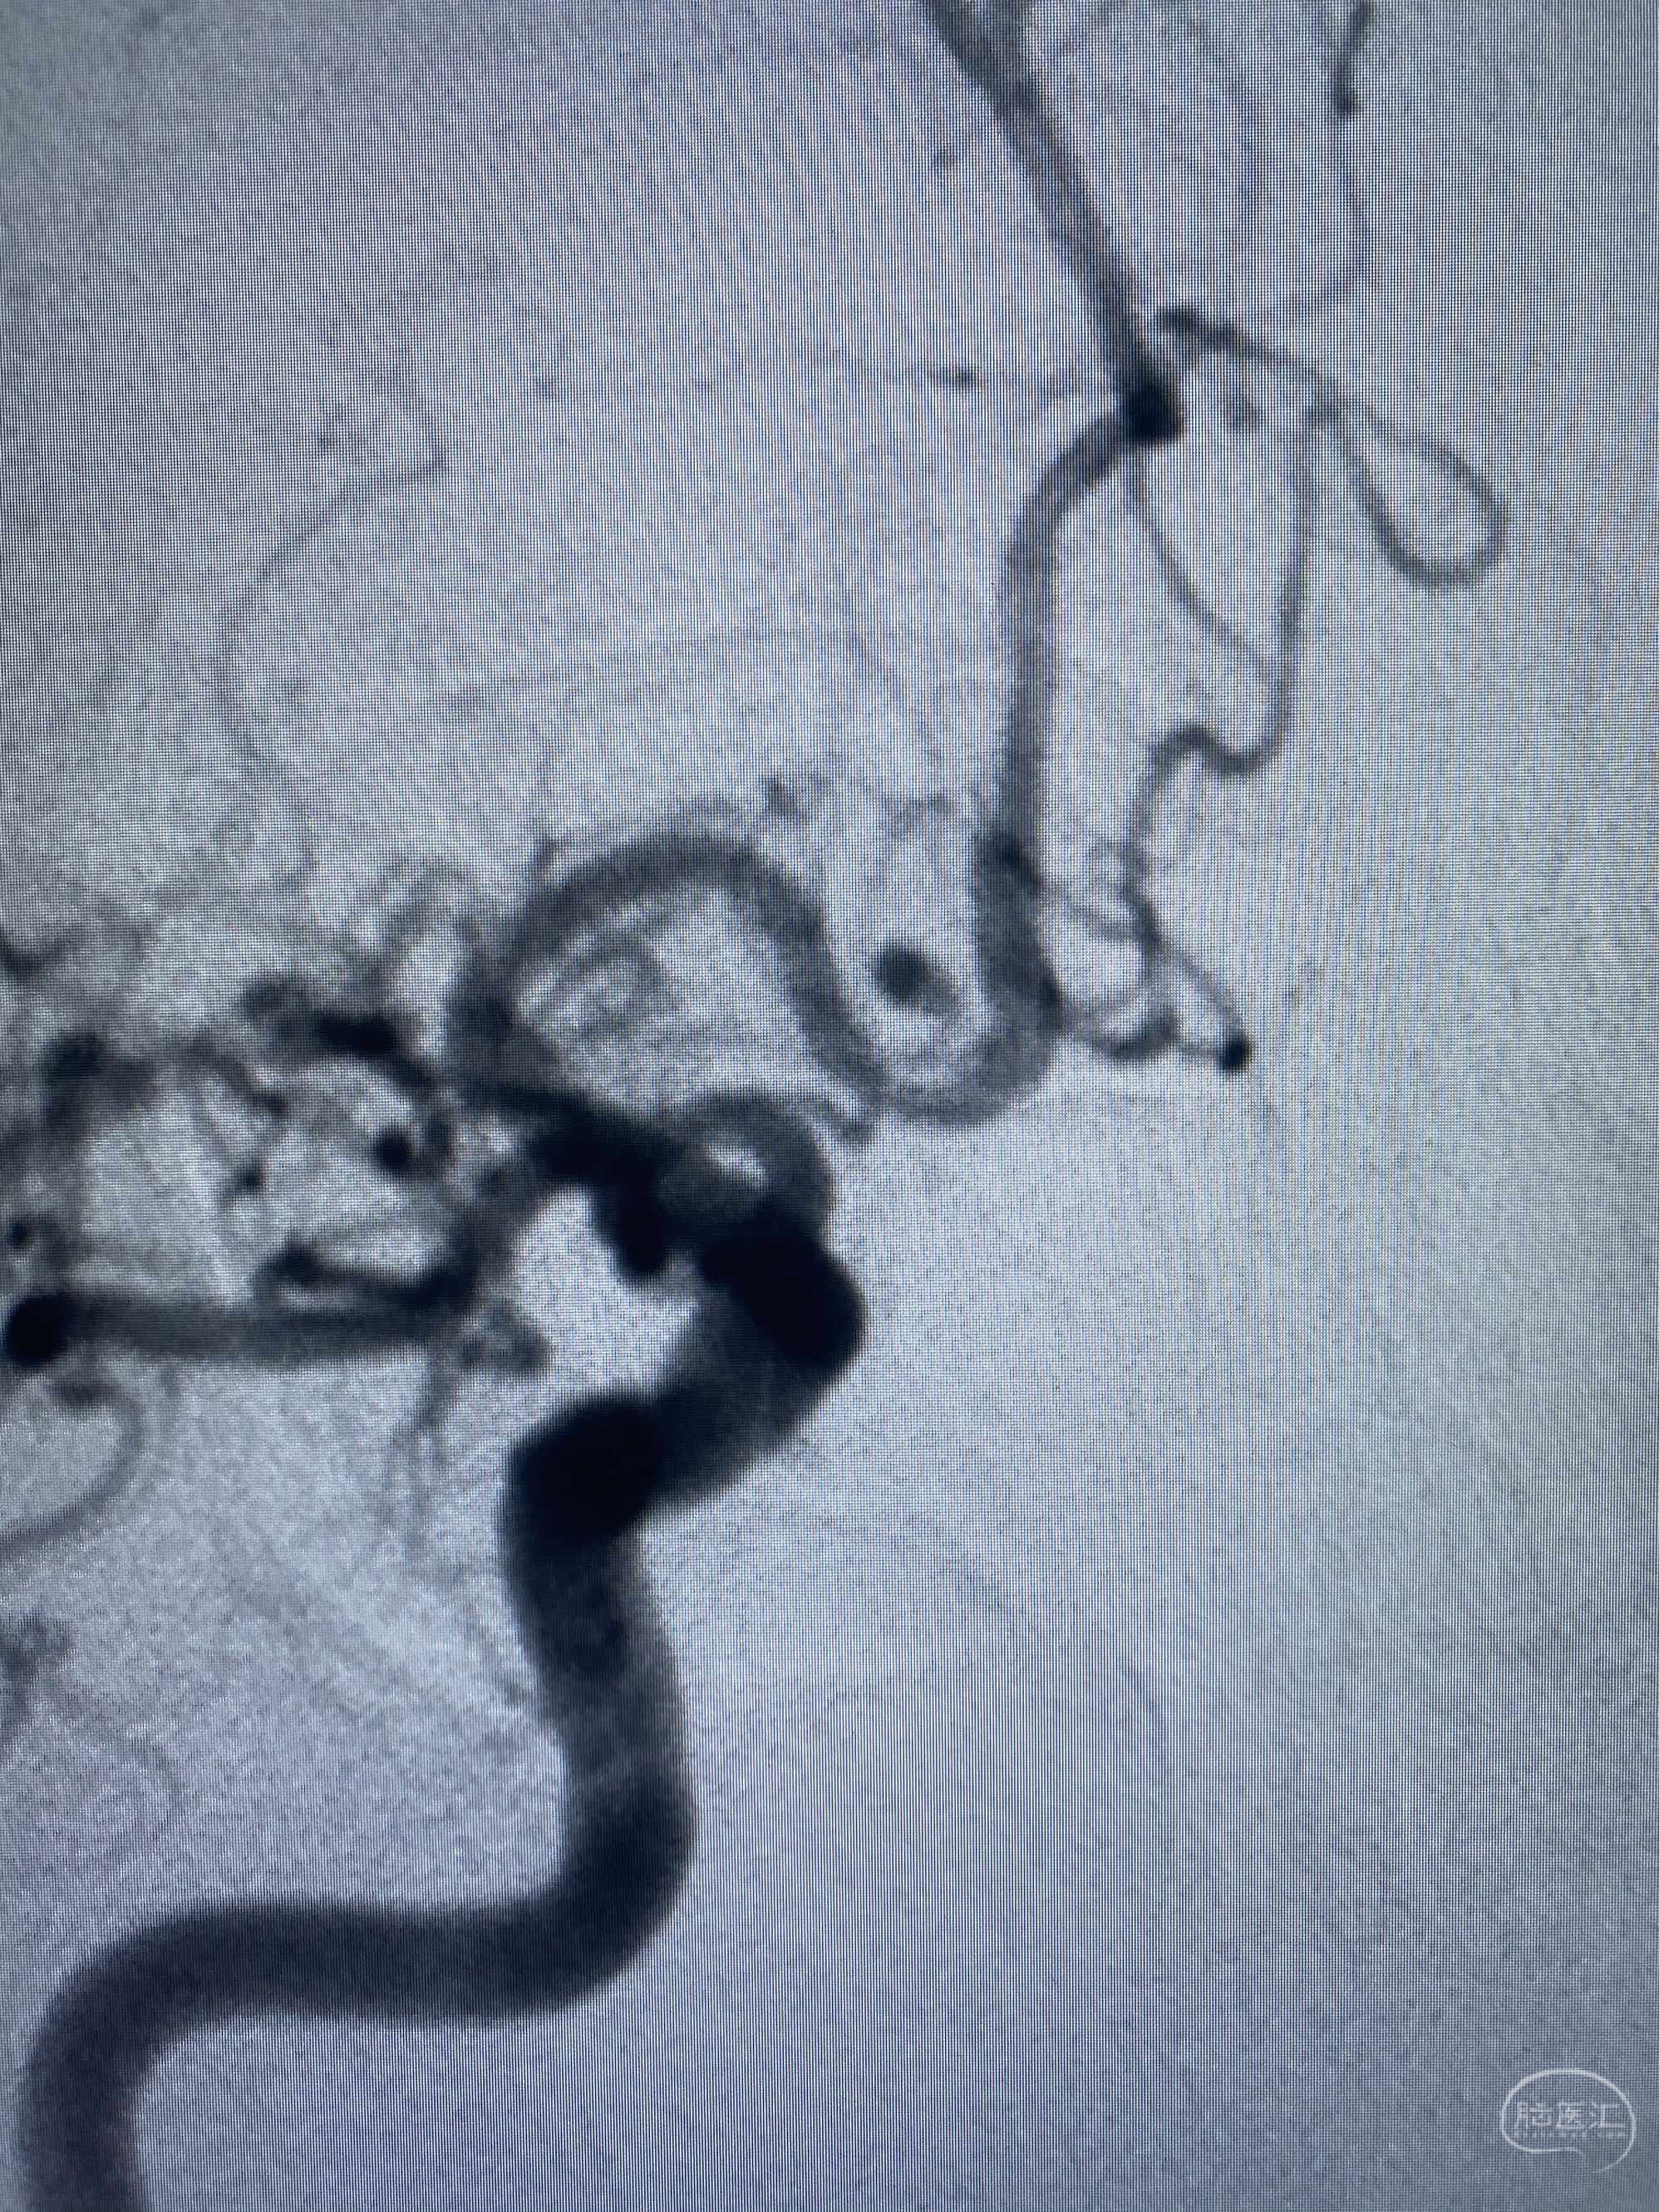

MLS,M79Y,sah,双侧MCA烟雾病,Heubner返动脉瘤,前交通段开窗,细支发出Heubner返动脉,瘤颈细长,瘤颈口比微导管细,弹簧圈2mmx3cm“隔山打牛”填塞治愈,Heubner返动脉保留。

Heubner返动脉是由大脑前动脉A1末端发出的豆纹动脉,由于走形和A1段相反,故称Heubner返动脉,该动脉梗塞可能引起尾状核头梗塞,引起偏瘫和面瘫,便身震颤等症状。